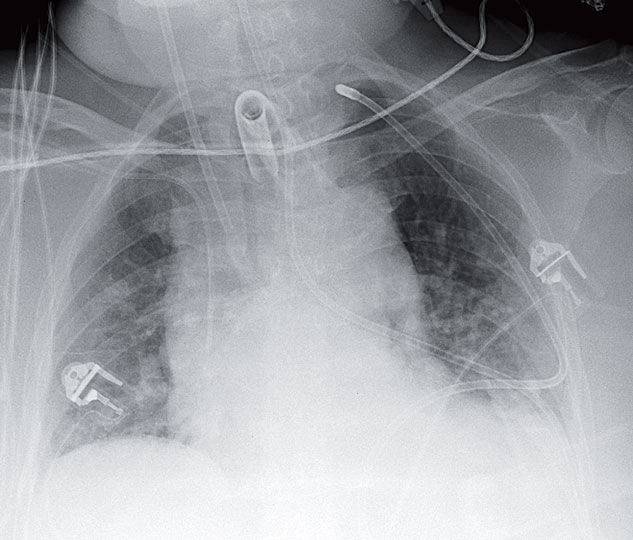

Woman with a History of a Mitochondrial Myopathy Post category:Spot Diagnosis Post published:February 14, 2026 Share on Facebook Share on X (Twitter) Share on Pinterest Share on Email Share on Reddit Woman with a History of a Mitochondrial Myopathy 72-year-old woman with a history of a mitochondrial myopathy receives this portable chest radiograph. What’s the diagnosis ? FULL CASE AND ANSWER Share on Facebook Share on X (Twitter) Share on Pinterest Share on Email Share on Reddit Read more articles Previous PostPink Plaques in a Healthy Infant Next PostPatient with Myasthenia Gravis and Hypoxia You Might Also Like Annular, Scaly, Blistering, Violaceous Plaque after use of Antibiotic August 19, 2021 Erythematous and Irregular Linear Streak Extending from the Hand to the Axilla December 21, 2021 Livedo Reticularis and Cyanosis of the Toes After CABG May 20, 2022